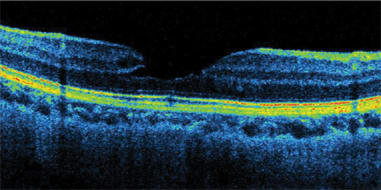

SDOCT does not skip or miss data points, as time domain OCT does because of its speed limitations. Thickness data between time domain scan lines is not actually measured, and values must be interpolated. No interpolation is needed with SDOCT. "We can see pathology that time domain OCT would have missed," Dr. Sharma says. "For example, SDOCT detects drusen or areas of subretinal fluid (Figure 1) that would have fallen between scans on time domain OCT. Also, it is much easier to discriminate pathology with SDOCT technology. For example, it is easier to discern the presence or absence of epiretinal membranes." (Figure 2)

Figure 2. An epiretinal membrane imaged by the Copernicus.